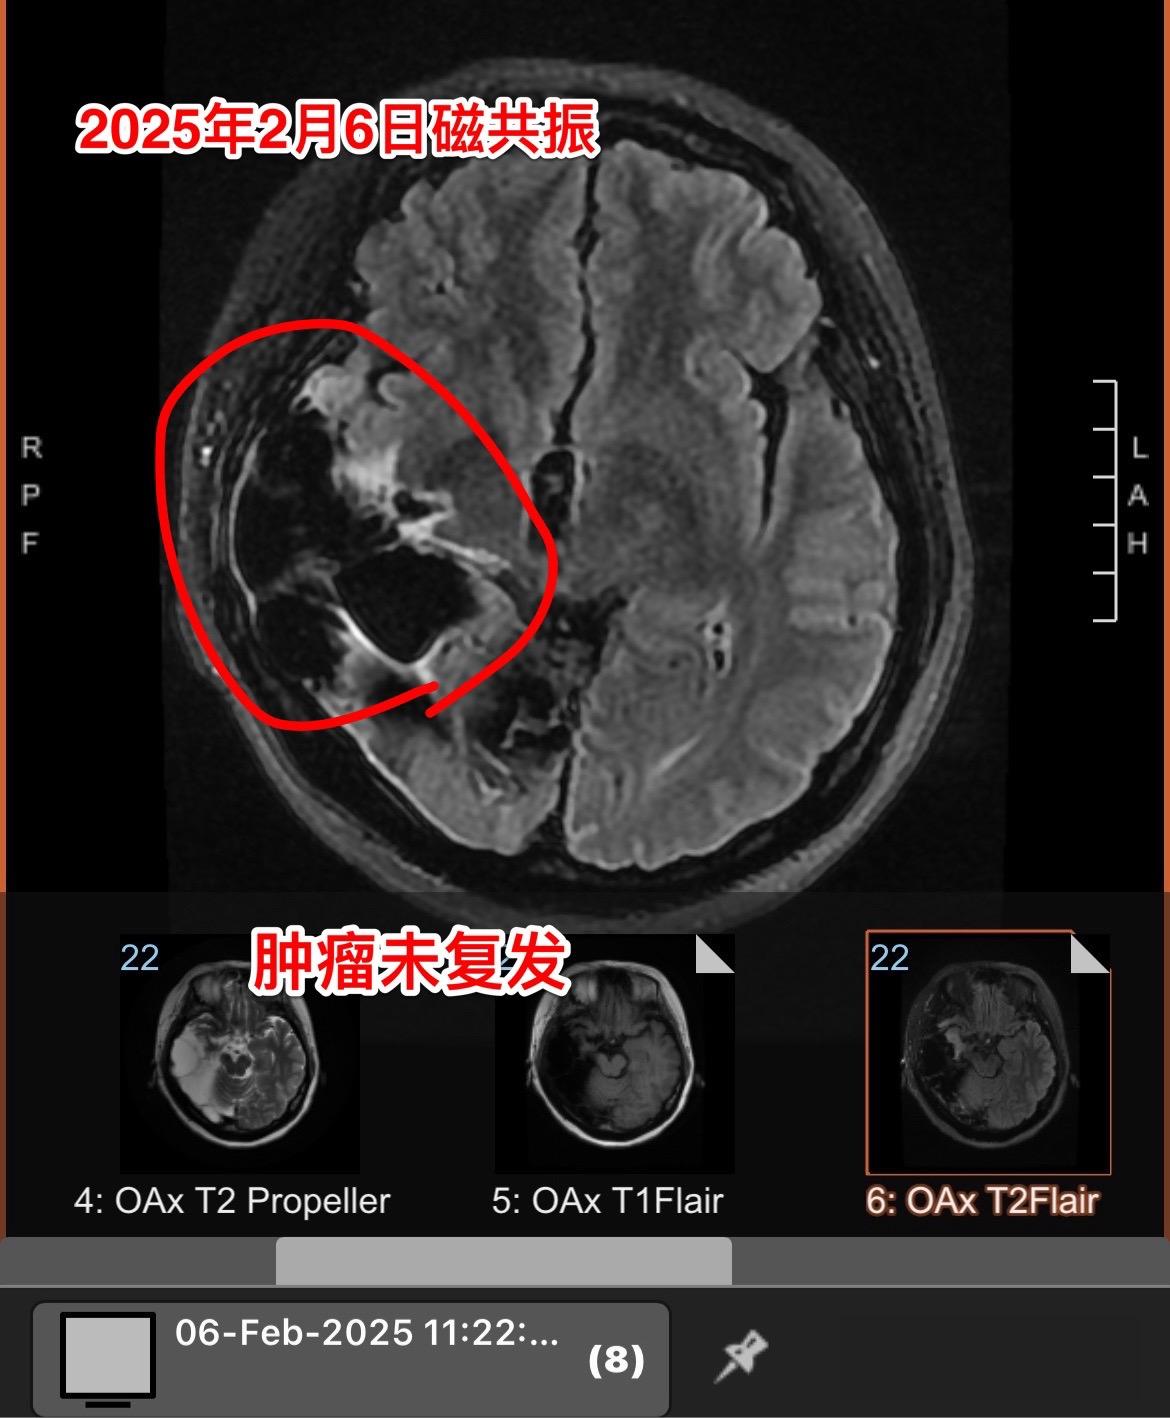

高级别胶质瘤要争取完全切除。新年上班第二天,今天收到一个胶质瘤病人手术后近5年复查的磁共振结果。 当时40岁的海城市女性于2020年5月因头痛发现脑部胶质瘤。于2020年5月15日在我科行手术切除肿瘤。 手术后病理报告为间变少突胶质瘤,没有找到合适的化疗药,出院后患者只作了脑部放疗,定期复查。 今天的磁共振显示肿瘤没有复发,太棒了👏